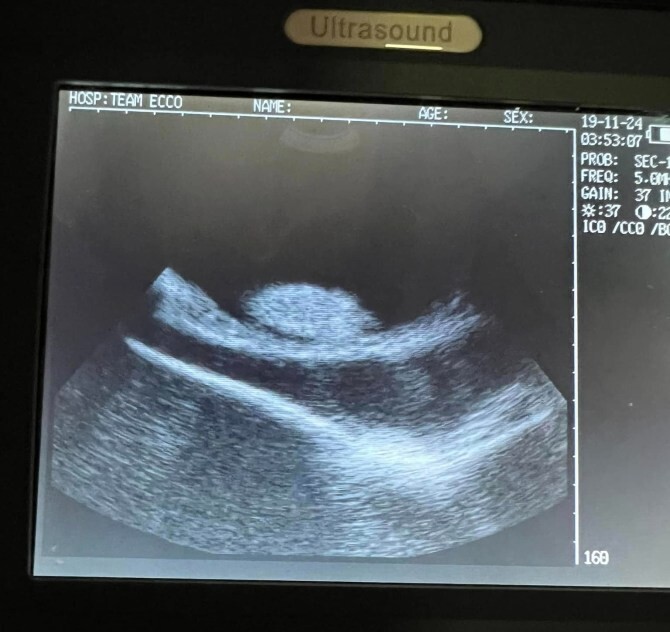

Charlotte will have children any day now, but her pregnancy came as a shock to everyone. Team ECCO staff noticed changes in the stingray's appearance back in September and thought it might be a tumor. An ultrasound examination showed that the female was in position.

"We've been doing ultrasounds on Charlotte since September. We saw multiple 'growths' inside and initially thought she had cancer," employee Ramer said Feb. 1.

“I contacted veterinarian Rob Jones, and he determined that the growths were eggs,” says Ramer. “We don’t have any male stingrays. He said that cases of parthenogenesis in stingrays are rare.”